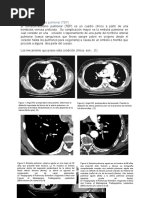

Semiología Pulmonar: Exploración y Diagnóstico

1. El documento describe los pasos del examen pulmonar, incluyendo la inspección, palpación, percusión y auscultación de los pulmones. 2. Se detallan los aspectos a considerar en cada etapa como la frecuencia respiratoria, tipos de respiración, sonidos pulmonares y más. 3. El objetivo es explorar de manera sistemática los pulmones mediante diferentes técnicas para detectar cualquier hallazgo anormal.